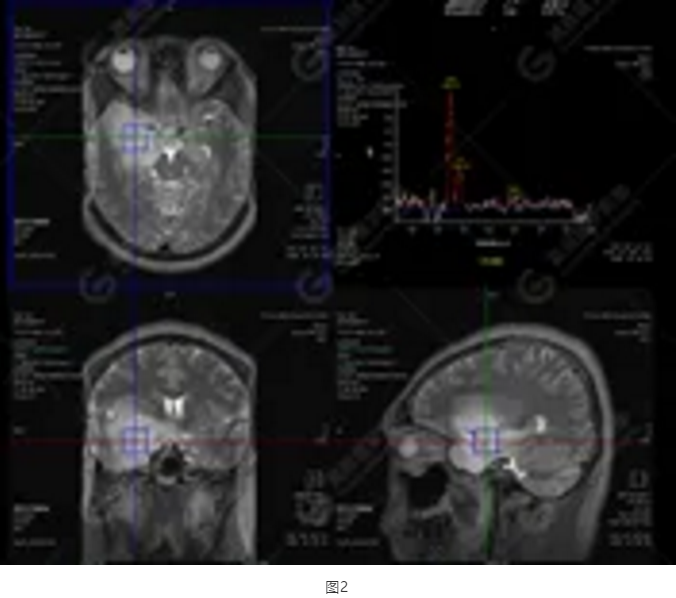

圖1為多體素MRS檢查,感興趣區(qū)為正常腦組織的MRS表現(xiàn)。圖2為單體素MRS,右側(cè)顳葉病灶內(nèi)NAA峰明顯下降,Cho峰明顯升高,NAA/Cr值為0.1,Cho/Cr值為3.64。